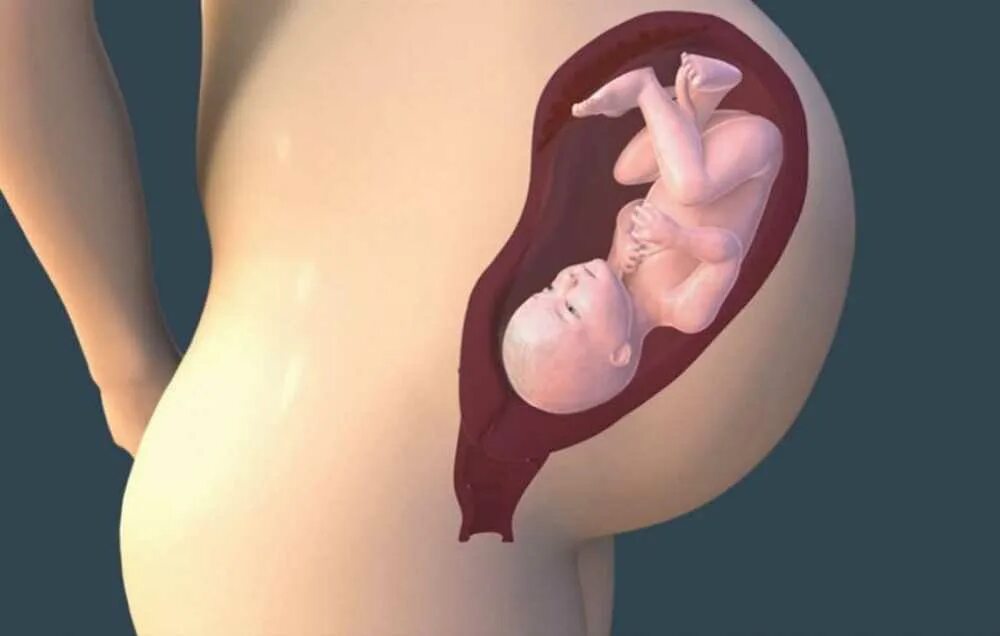

Ребенок 36 недель беременности в животе